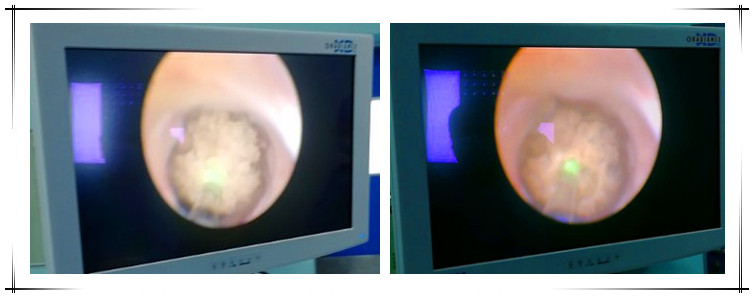

泌尿系统结石是泌尿外科、急诊门诊最常见的疾病之一,以往对于药物和体外震波治疗无效的患者ー般采用开刀手术取石方法,会给患者带来新的创伤。近期,我院普外科应用新近购置的钬激光设备成功为4例输尿管结石患者施行了...[详细]